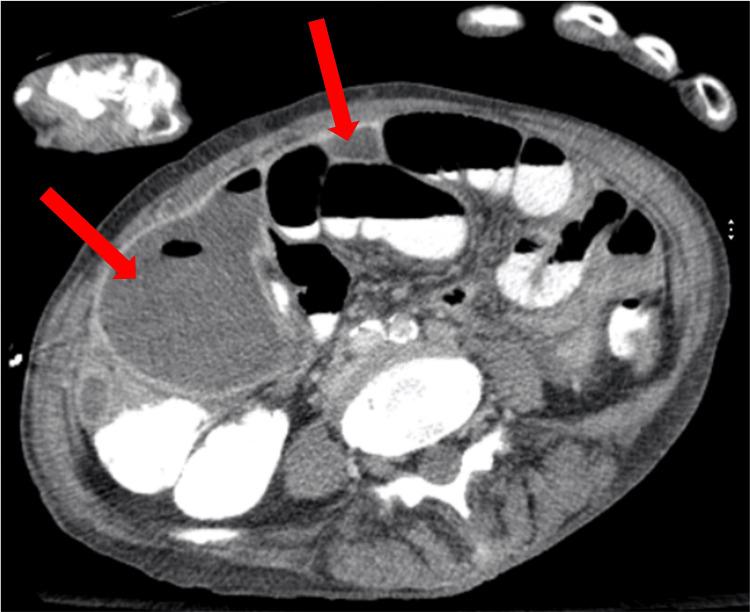

This is the case of a 65-year-old female patient with chronic obstructive pulmonary disease (COPD) who presented following a fall and was found to have a humeral fracture. Initial evaluation showed sepsis of unknown origin, leukocytosis, and elevated inflammatory markers. Persistent abdominal pain prompted imaging studies, which showed multiloculated intra-abdominal abscesses. Ultrasound-guided drainage yielded . Antibiotics, along with percutaneous drainage, resulted in a good clinical response. Follow-up imaging revealed a decrease in the abscess size, with no evidence of a fistula. This case highlights the diagnostic challenges of intra-abdominal abscesses and the importance of timely imaging in patients presenting with sepsis and nonspecific symptoms.

这是一名65岁患有慢性阻塞性肺疾病(COPD)的女性患者的病例,她在跌倒后就诊,被发现有肱骨骨折。初步评估显示有不明原因的脓毒症、白细胞增多和炎症标志物升高。持续的腹痛促使进行影像学检查,结果显示有多处腹腔内脓肿。超声引导下引流取得了……抗生素联合经皮引流产生了良好的临床反应。后续影像学检查显示脓肿大小减小,没有瘘管的迹象。该病例突出了腹腔内脓肿的诊断挑战以及对出现脓毒症和非特异性症状患者进行及时影像学检查的重要性。